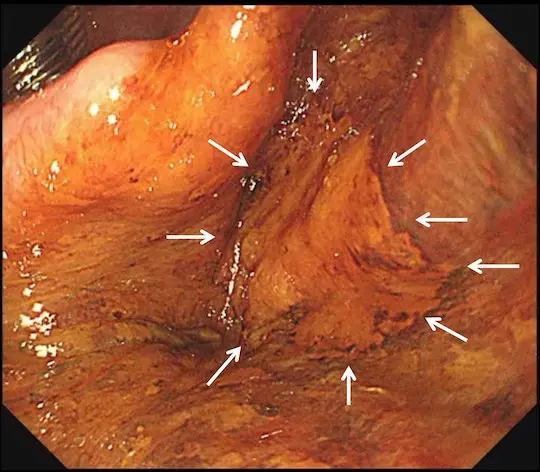

病変の切除を完了しました。白い矢印の内側が切除部位です。キズが出来ますが、時間の経過とともに自然に治って閉じます。

体外に摘出した咽頭癌をピンで張り付けて伸ばしています。

左(通常観察):白い点は、病変のすぐ外側に電気メスで付けたマークです。全周性にマークが認められ、切除予定だった範囲を切除できたことが分かります。

右(ヨード染色後):薬液(ヨード)で染色すると、黄色矢印内に色の違う部分が出てきます。この部分が咽頭癌です。病理検査(顕微鏡での分析)で咽頭癌は完全に切除されており、治癒と判定されました。